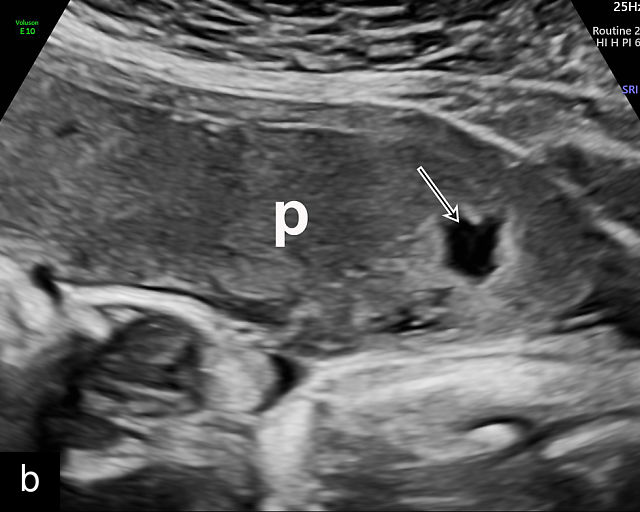

Placenta previa and low-lying placenta

In most pregnancies, the placenta implants in the upper part of the uterus. However, when the placenta implants in the lower uterine segment and overlies the cervix, it results in a condition called placenta previa, meaning the placenta is positioned ahead of the fetus in the birth canal.49 This positioning poses a serious risk during labor, as cervical dilation can cause premature placental separation, leading to severe, life-threatening bleeding for the pregnant patient.50,51 To prevent this hemorrhage, patients with placenta previa must be delivered by cesarean section before the onset of labor.51 Placenta previa complicates approximately 0.4% (1 in 250) of pregnancies at delivery.52 The strongest risk factor for placenta previa is a history of prior cesarean delivery.53,54,55 Maternal smoking, advanced maternal age and assisted reproductive technologies are also strong risk factors for placenta previa.56,57,58,59

Historically, placenta previa was most often identified in the early third trimester when patients presented with painless vaginal bleeding.49,60,61 However, with the widespread use of obstetric ultrasound in the second trimester, nearly all cases of placenta previa are now diagnosed incidentally in asymptomatic patients during routine scans. Notably, approximately 90% of placenta previa cases diagnosed in the second trimester will resolve by term due to placental ‘migration’ as the uterus grows.51,61,62,63,64,65 Thus, when placenta previa is diagnosed in the second half of pregnancy, the patient should have an examination close to delivery to determine whether the placenta previa is persistent or whether it has resolved. Generally, when a placenta previa is found at 20 weeks, a repeat ultrasound should be performed at about 32 weeks. In cases that persist at 32 weeks, a repeat scan should be performed around 36 weeks of gestation.66

In the past, placenta previa was classified as complete, partial, marginal or low-lying.50,61 However, with advancements in ultrasound technology allowing precise assessment of the relationship between the placenta and the internal cervical os, the classification has been simplified.67 Placenta previa now refers to cases in which the placenta overlies the internal os to any degree, while low-lying placenta describes cases in which the lower placental edge lies within 2 cm of the internal os (Figure 5).51,66,67

5

Placenta previa and low-lying placenta. (a) Transabdominal grayscale ultrasound image suspicious for placenta previa. The placenta (PL) appears to overlie the internal cervical os (CX). Note the time stamp: 2:19:37. (b) Transvaginal ultrasound of the same patient taken approximately 50 minutes later. Note the time stamp: 3:10:25. The internal os and the lower placental edge are both clearly seen, and the placenta does not overlie the internal os. Because the lower placental edge is 1.93 cm from the internal os, it will likely resolve by the third trimester. (c) Transabdominal grayscale ultrasound of placenta previa. The placenta (p) covers the cervix, but the cervix, especially the internal os, cannot be visualized due to shadowing. (d) Transabdominal grayscale ultrasound of placenta previa. The placenta (p) covers the cervix (c) but shadowing obscures adequate visualization. The internal os is indicated by the arrow. (e) False-positive image of placenta previa on transabdominal grayscale ultrasound. The bladder (b) is full, pushing the anterior and posterior walls of the lower uterine segment (ls) together making it appear that the placenta (p) overlies the internal os of the cervix. In reality, the line depicted by the arrowheads is where the anterior and posterior walls of the lower segment are in proximity to each other. The cervix is much lower and is obscured by shadowing (c). (f) Transabdominal grayscale ultrasound image of placenta previa. The placenta (p) covers the cervix (c), but the cervix, especially the internal os, cannot be visualized due to shadowing. b, bladder. (g) Transvaginal grayscale ultrasound image of placenta previa. The placenta (p) completely covers the internal os (arrow) of the cervix (c). The internal os can be seen clearly. h, fetal head. (h) Transvaginal grayscale ultrasound image of posterior low-lying placenta (p). The lower placental edge is clearly seen and is 1.56 cm from the internal os (arrow) of the cervix (c). The placental edge and the internal os are clearly seen. h, fetal head. (i) Transvaginal grayscale ultrasound image of a posterior placenta previa (p). The internal cervical os is clearly seen (arrow). c, cervix. (j) Transvaginal grayscale ultrasound image of an anterior placenta previa (p). The internal cervical os is clearly seen (arrow). c, cervix; h, fetal head. (k) Transvaginal grayscale ultrasound image of a posterior placenta that was thought to be low-lying on transabdominal sonography but could not be adequately assessed. This examination clearly shows the lower edge of the placenta (p) to be 2.18 cm from the internal os (arrow) of the cervix, firmly establishing that the placenta is not low-lying and allowing the patient to undergo labor safely and deliver vaginally. c, cervix. (l) Transvaginal grayscale ultrasound image of placenta previa. The placenta (p) completely covers the internal os (arrow) of the cervix (c). The internal os can be seen clearly.

This distinction is critical in determining the mode of delivery.49,51 All patients with placenta previa persisting into late pregnancy require cesarean delivery to avoid complications such as severe bleeding.50,60,61 Studies suggest that patients with a lower placental edge located more than 1 cm from the internal os may safely attempt a vaginal delivery without a significant increase in bleeding risk.68,69,70,71

In patients with placenta previa and one or more prior cesarean deliveries, careful evaluation is necessary to rule out placenta accreta spectrum disorders, in which the placenta abnormally adheres to or implants deeply into the uterine wall.50,60

Most cases of placenta previa will be suspected prenatally by transabdominal ultrasound.49 However, this approach has several limitations and may be inaccurate.72,73,74 because the relationship between the placenta and the internal cervical os may be difficult to assess by transabdominal ultrasound.72,73,74 The bladder may be full, pushing the anterior and posterior walls of the lower uterine segment together, falsely creating the impression of a placenta previa (Figure 5e).61 There may be considerable shadowing, including by the fetal presenting part, which may limit the accuracy of transabdominal ultrasound (Figure 5d,f).75 Posterior placentas may be more difficult to assess.

Transvaginal ultrasound overcomes these limitations (Figure 5g–l).72,73,74,76 The probe is inserted into the vagina and therefore is closer to the region of interest.51,61 In addition, transvaginal transducers have higher frequencies and superior resolution compared to transabdominal transducers. Transvaginal ultrasound is safe and is not associated with increased bleeding.72,73,74,75,76 As such, transvaginal ultrasound should be the imaging modality of choice whenever there is suspicion of placenta previa.49,67,77